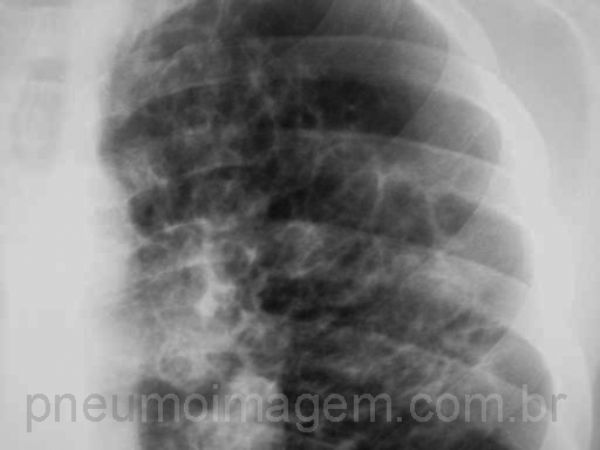

A Fibrose Cística (ou Mucoviscidose) é uma doença genética rara associada a complicações em vários órgãos. O pulmão é o mais afetado e é o responsável pelo óbito precoce em mais de 80% dos casos. O pâncreas também é afetado em mais de 70% dos pacientes e leva às manifestações clínicas da insuficiência pancreática exócrina, com esteatorreia e desnutrição. Fígado e seios da face também podem estar envolvidos. Na Fibrose Cística (FC), as bronquectasias costumam ser centrais e predominar nos lobos superiores.

Cystic Fibrosis (or Mucoviscidosis) is a rare genetic disease associated with complications in various organs. The lung is the most affected and is responsible for early death in more than 80% of cases. The pancreas is also affected in more than 70% of patients and leads to the clinical manifestations of exocrine pancreatic insufficiency, with steatorrhea and malnutrition. Liver and sinuses may also be involved. In Cystic Fibrosis (CF), bronchiectasis is usually central and predominates in the upper lobes.

Detalhe da radiografia em PA ilustrada na imagem anterior e que demonstra as dilatações brônquicas no lobo superior esquerdo.

Detail of the radiography in PA shown in the previous image and demonstrating the bronchial dilatations in the upper left lobe.